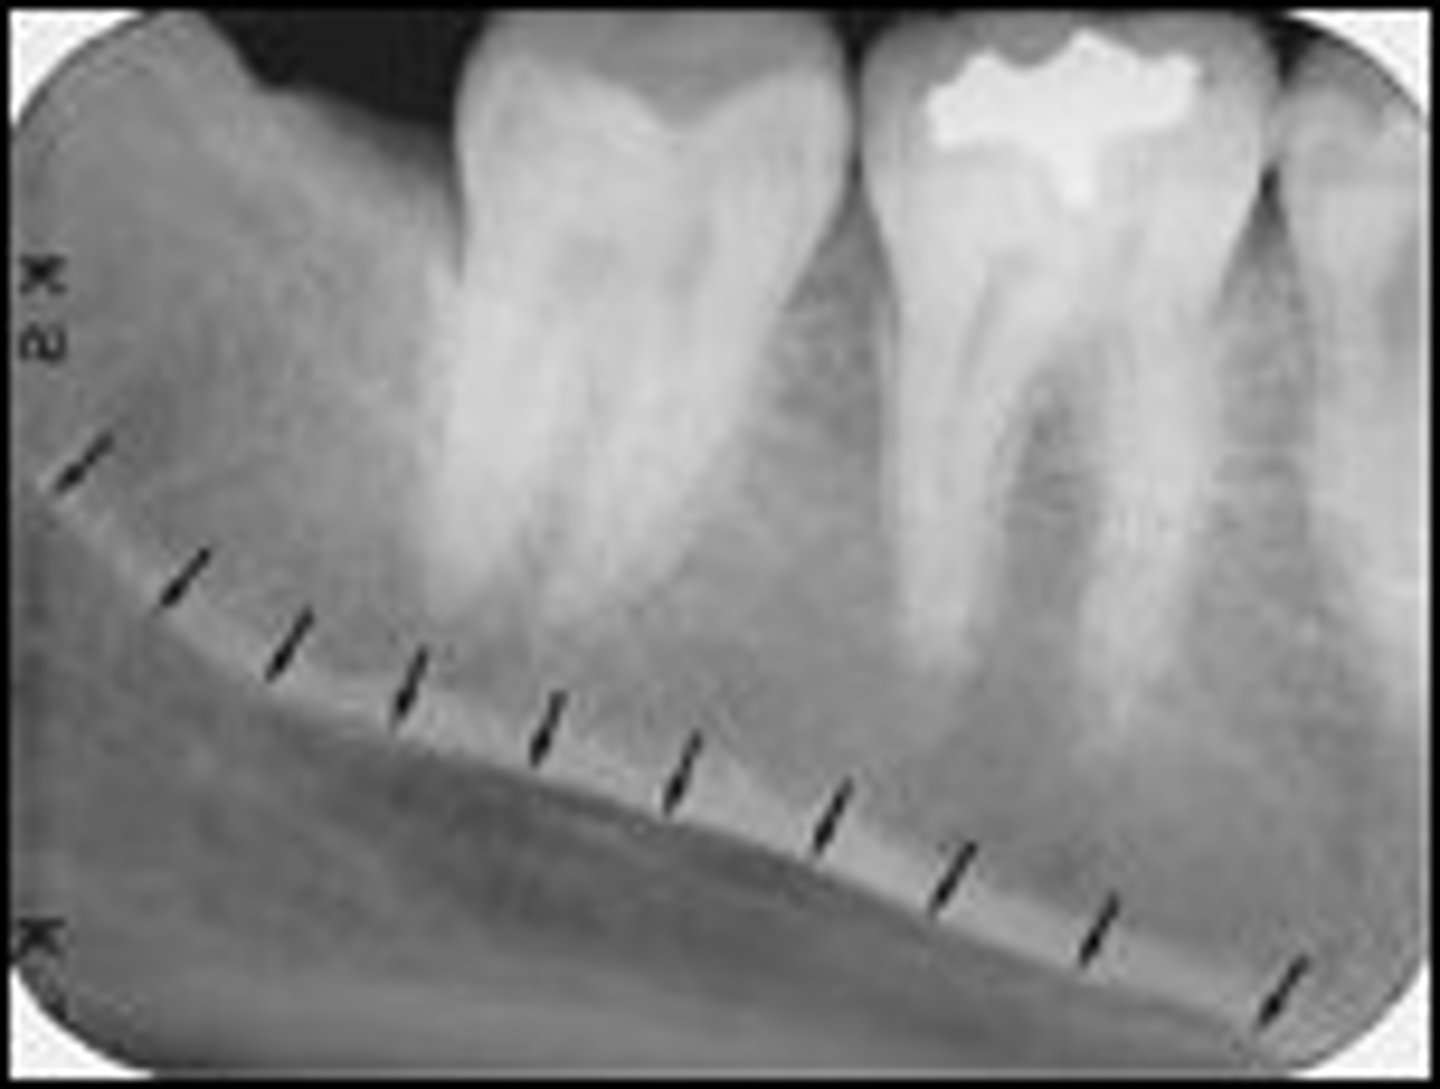

stepwedge

tests the output of an x-ray machine

determines amounts of radiation reaching the film by measurements of film density

tests when to change solutions

lead foil attached to cardboard or tongue depressor